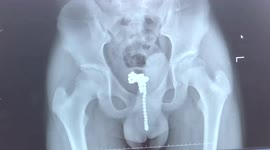

Chinese doctor removes pin from 7-month-old boy's body after he swallowed it

A doctor in southern China removed a pin from a 7-month-old boy’s body after he swallowed it.

The video, captured in the city of Chengdu in Sichuan Province on April 3, shows a doctor named Liu Yinghua using a tool to take a 2-centimetre-long pin out of a baby’s body during surgery.

According to reports, the baby mistakenly swallowed the pin when he was playing.

Fortunately, the pin was removed successfully and the baby has discharged from the hospital after two days of observation.